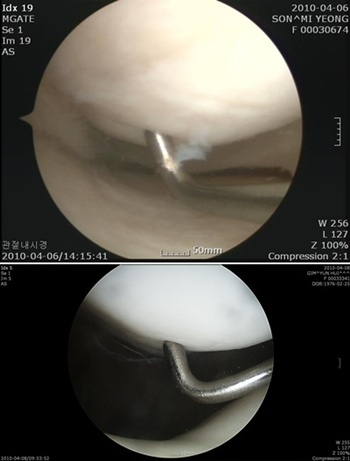

권오룡 소장은 “PRP주사요법은 연골세포 활성도가 높은 것이 장점”이라며 “ 무릎 뿐만 아니라, 초·중기 퇴행성관절염, 어깨회전근개질환, 족저근막염, 테니스 엘보 환자 등에도 폭넓게 적용할 수 있는 것이 특징이다”라고 덧붙였다. /강진수 객원기자 osenlife@osen.co.kr <사진> 연골연화증(위)과 정상인 경우의 비교.